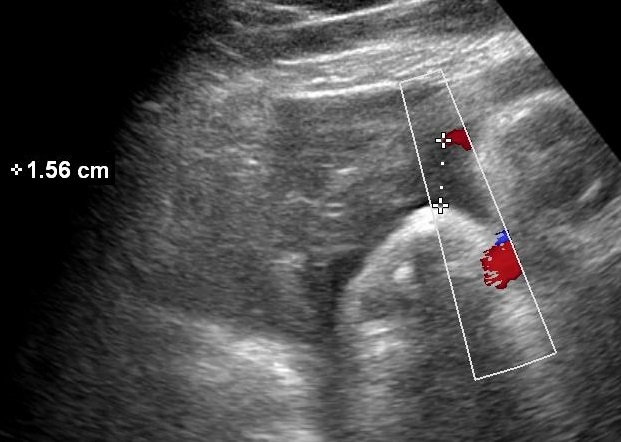

- Amniotic Fluid Index (AFI)

The measurement is performed with the ultrasound probe at a right angle with the uterine wall. Measurements should exclude the umbilical cord or fetal parts. The width of each measured pocket must be at least 1 cm. Normal values range between 2-8 cm. It is also the preferred method for estimating the amniotic fluid volume in twin pregnancies.